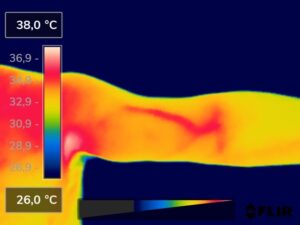

Como na sequência de termogramas abaixo de um paciente do sexo masculino, de 44 anos, sem comorbidades e praticante de atividade física que apresentou fortes dores em braço esquerdo (com irradiação para antebraço) após treino de musculação. Esta dor chegou a ser incapacitante, pois impossibilitava inclusive o paciente a realizar atividades de vida diárias como pegar um copo de água.

Após a realização de uma Análise Termofuncional©®, foi detectado alterações térmicas em “linha”, margeando as fibras musculares e tendíneas inferiores (insercionais) bicipitais. Estas alterações também aventaram a hipótese de dilatação venosa, por alguma reação inflamatória local. Foi realizado então aplicação de laserterapia através da Técnica Termoguiada, que acabou por promover a completa analgesia em 24 horas após aplicação.